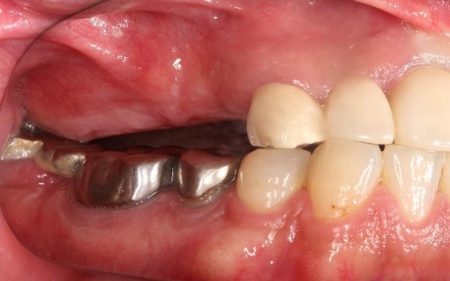

治療前

拝見したところ、右上奥歯4本が欠損しており、その影響で全体の噛み合わせのバランスが崩れていました。

加えて、噛んだときに上下の歯の中心がずれており、顔貌のゆがみにもつながっています。

欠損部が多い状態が長期間続いたことで噛み合わせが低く、新しい歯を入れるための高さも不足していました。

また、右上前歯も1本欠損しており、両隣の歯を土台として橋を渡すように連結した被せ物「ブリッジ」が装着されていましたが、土台となっている右上前歯2本(中切歯、犬歯)が割れており、温存が難しい状態です。

さらに、劣化してうまく適合していない被せ物、詰め物、既存のインプラントが複数見られ、これらも噛み合わせを乱す原因となっていました。

加えて全体的に歯周病も進行しており、骨が溶けている部分も確認できます。